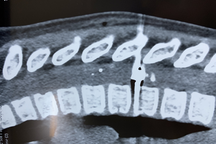

Viên đạn găm vào cung mày phải và xuyên qua sọ bé trai (Ảnh: BV).

Bác sĩ Lê Quang Mỹ, khoa Ngoại Thần kinh, Bệnh viện Nhi đồng 2 cho biết, bệnh nhi nhập viện trong trạng thái tỉnh táo, có một vết thương ở chân mày phải đã được khâu tạm ở tuyến trước. Ảnh chụp cắt lớp sọ não thấy có dị vật kim loại nằm ngay cạnh mắt phải, găm vào xương sọ bệnh nhi.

"Đây là tai nạn rất nghiêm trọng, nhưng may mắn dị vật nằm ở vị trí không bị ảnh hưởng tới mắt hoặc não. Bé được gây mê, phẫu thuật mở vết thương kiểm tra và lấy được viên đạn chì, kích thước 5mm" - bác sĩ chia sẻ.